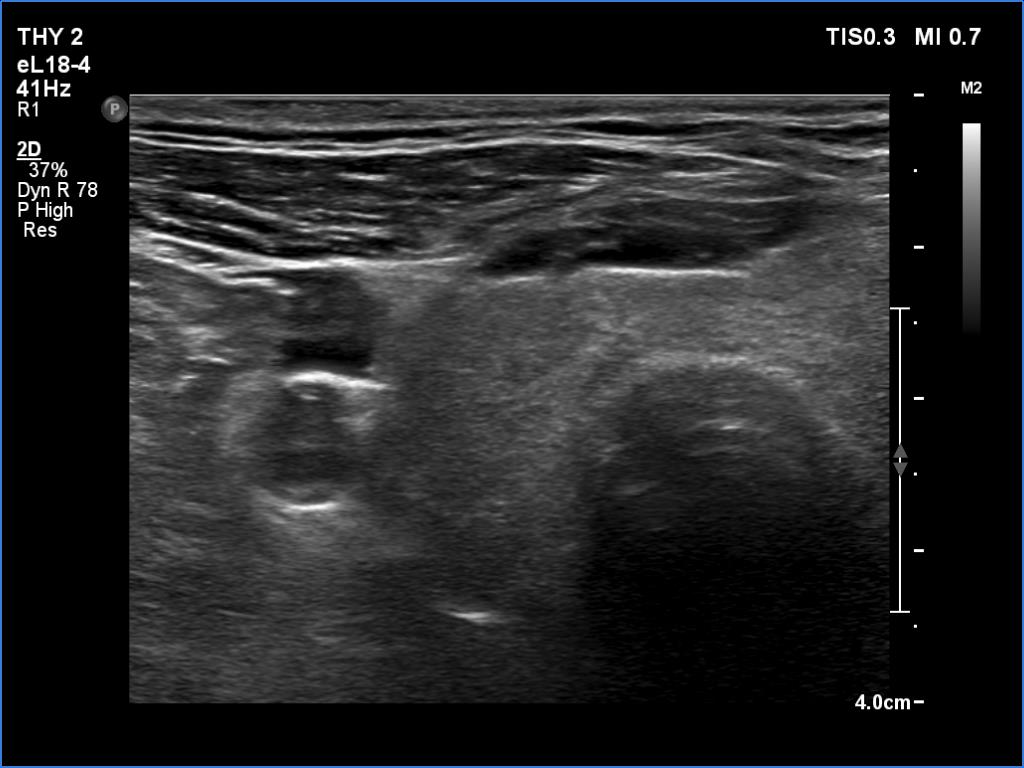

Ultrasonography. The right lobe was echonormal and intact. A large mass occupied almost the entire left lobe. On this side, normal thyroid tissue could only be identified in the dorsal part. The mass was composed of echonormal and hypoechoic areas, had macrocalcifications, irregular intranodular vascularity and proved to be very hard on elastography. There were multiple lymph nodes in III, IV and V left neck compartments. One of the nodes was in close proximity to the jugular vein and was suspicious of having broken into the vessel. The trachea was significantly narrowed at the lower level of the thyroid.

US-guided aspiration was performed from the thyroid mass and from the lymph node presented in the images. Cytology resulted in all three cases in metastatic carcinoma. Wash out thyroglobulin levels were 2.02 and 8.19 ng/L in the thyroid mass and in the neck lymph node, respectively.

2. There are several remarkable findings in this case, e.g., the destruction of the left lobe by the tumor, the elastography pattern, the relation of the largest metastatic lymph node and the jugular vein, the ultrasound demonstration of the trachea' stricture.